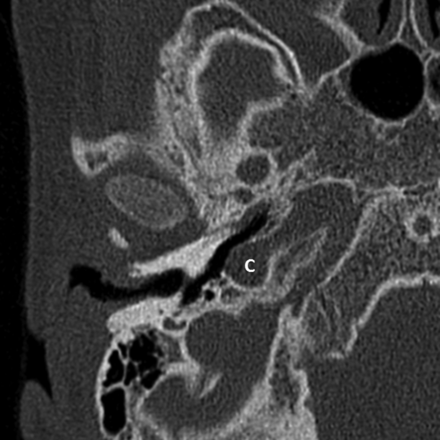

Last, in 5 ears (10%) (4 patients), a dehiscence of the carotid canal was present (Fig 6). The vestibular aqueduct and the facial nerve were normal in all cases, except in the ear with an aural atresia, where the facial nerve could not be identified.

Axial CT image of the right mastoid bone showing a carotid canal dehiscence (C).